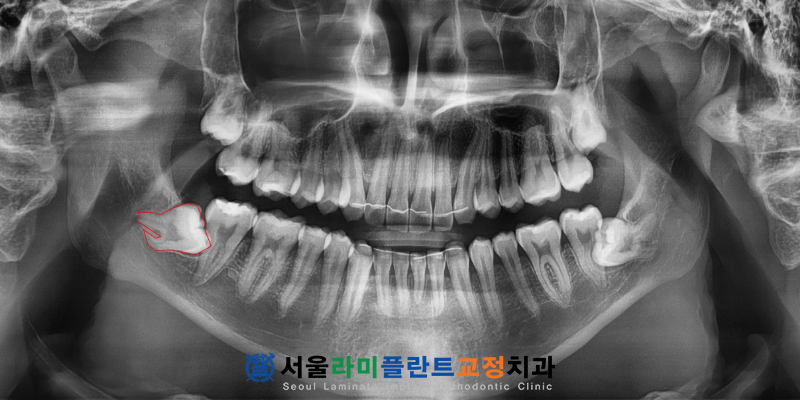

무엇보다 큰 문제는 사랑니의 뿌리가

아래턱 신경관인 하치조신경관과

겹쳐 보일 정도로 매우 가깝게

인접해 있다는 점이었습니다.

특히 하치조신경관과 치아 뿌리가 겹쳐 있는

매복 사랑니의 경우 발치 과정에서

뿌리가 부러지거나 조각이

남을 확률이 매우 높았으며

신경 손상의 위험성도 배제할 수 없었습니다.

이에 따라 보다 정밀한 입체 분석을 위해

CT촬영을 진행하여 치아의 굴곡진 각도와

신경관의 위치 및 거리를

입체적으로 파악하였습니다.

동탄치과 서울라미플란트치과교정과치과는

분석된 데이터를 바탕으로

치아를 분할하여 발치할 계획을 세웠으며

신경에 가해지는 압박을 가능한 줄이면서

휘어진 뿌리 끝까지 손상 없이

꺼낼 수 있도록 신중하게 접근하였습니다.